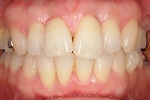

CASE1

前歯の歯並びが悪いのが一番気になります。

右側では良く噛めません↓(16歳/女性)

||||||||

概要・担当医コメント:叢生・右側咀嚼障害↑

マルチブラケット装置/動的治療期間26ヶ月(23回)

/費用概算:60万円

高校の部活も矯正も両方頑張れたそうです。

上顎右側の小臼歯を1本のみ抜歯させていただき,あとは上下の歯列アーチ形態の修正にて矯正できました。